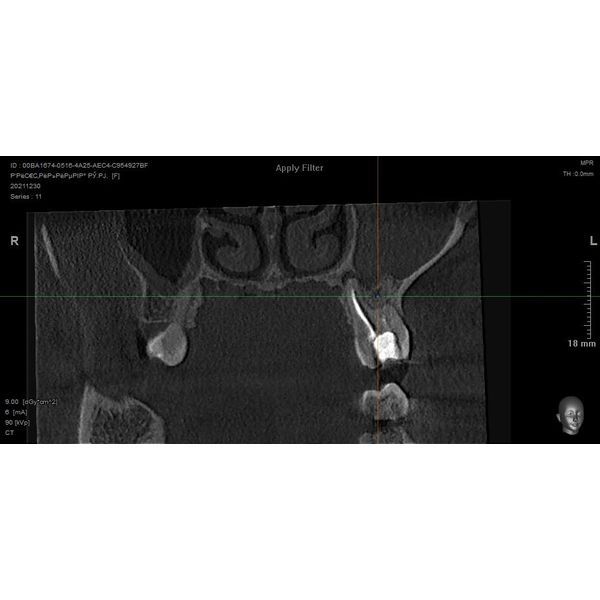

На конусно-лучевой компьютерной томографии (КЛКТ) отмечалось отсутствие воздушности в верхнечелюстной пазухё (ВЧП) слева, она была полностью заполнена однородным содержимым. Данных за соустье не было. Слизистая ВЧП справа была увеличена до 4–5 мм.

На верхушках корней зуба 2.6 отмечалось расширение периодонтальной щели до 1–2 мм. Корни близко прилегали к ВЧП слева. Ранее проводилось эндодонтическое лечение:

- первый медиально-букальный (MB1) канал на две трети заполнен рыхлым гипохромным материалом;

- второй медиально-букальный (MB2) канал закрыт, просвет прослеживался слабо;

- дистальный (D) и нёбный (P) каналы рыхло заполнены на всю длину.